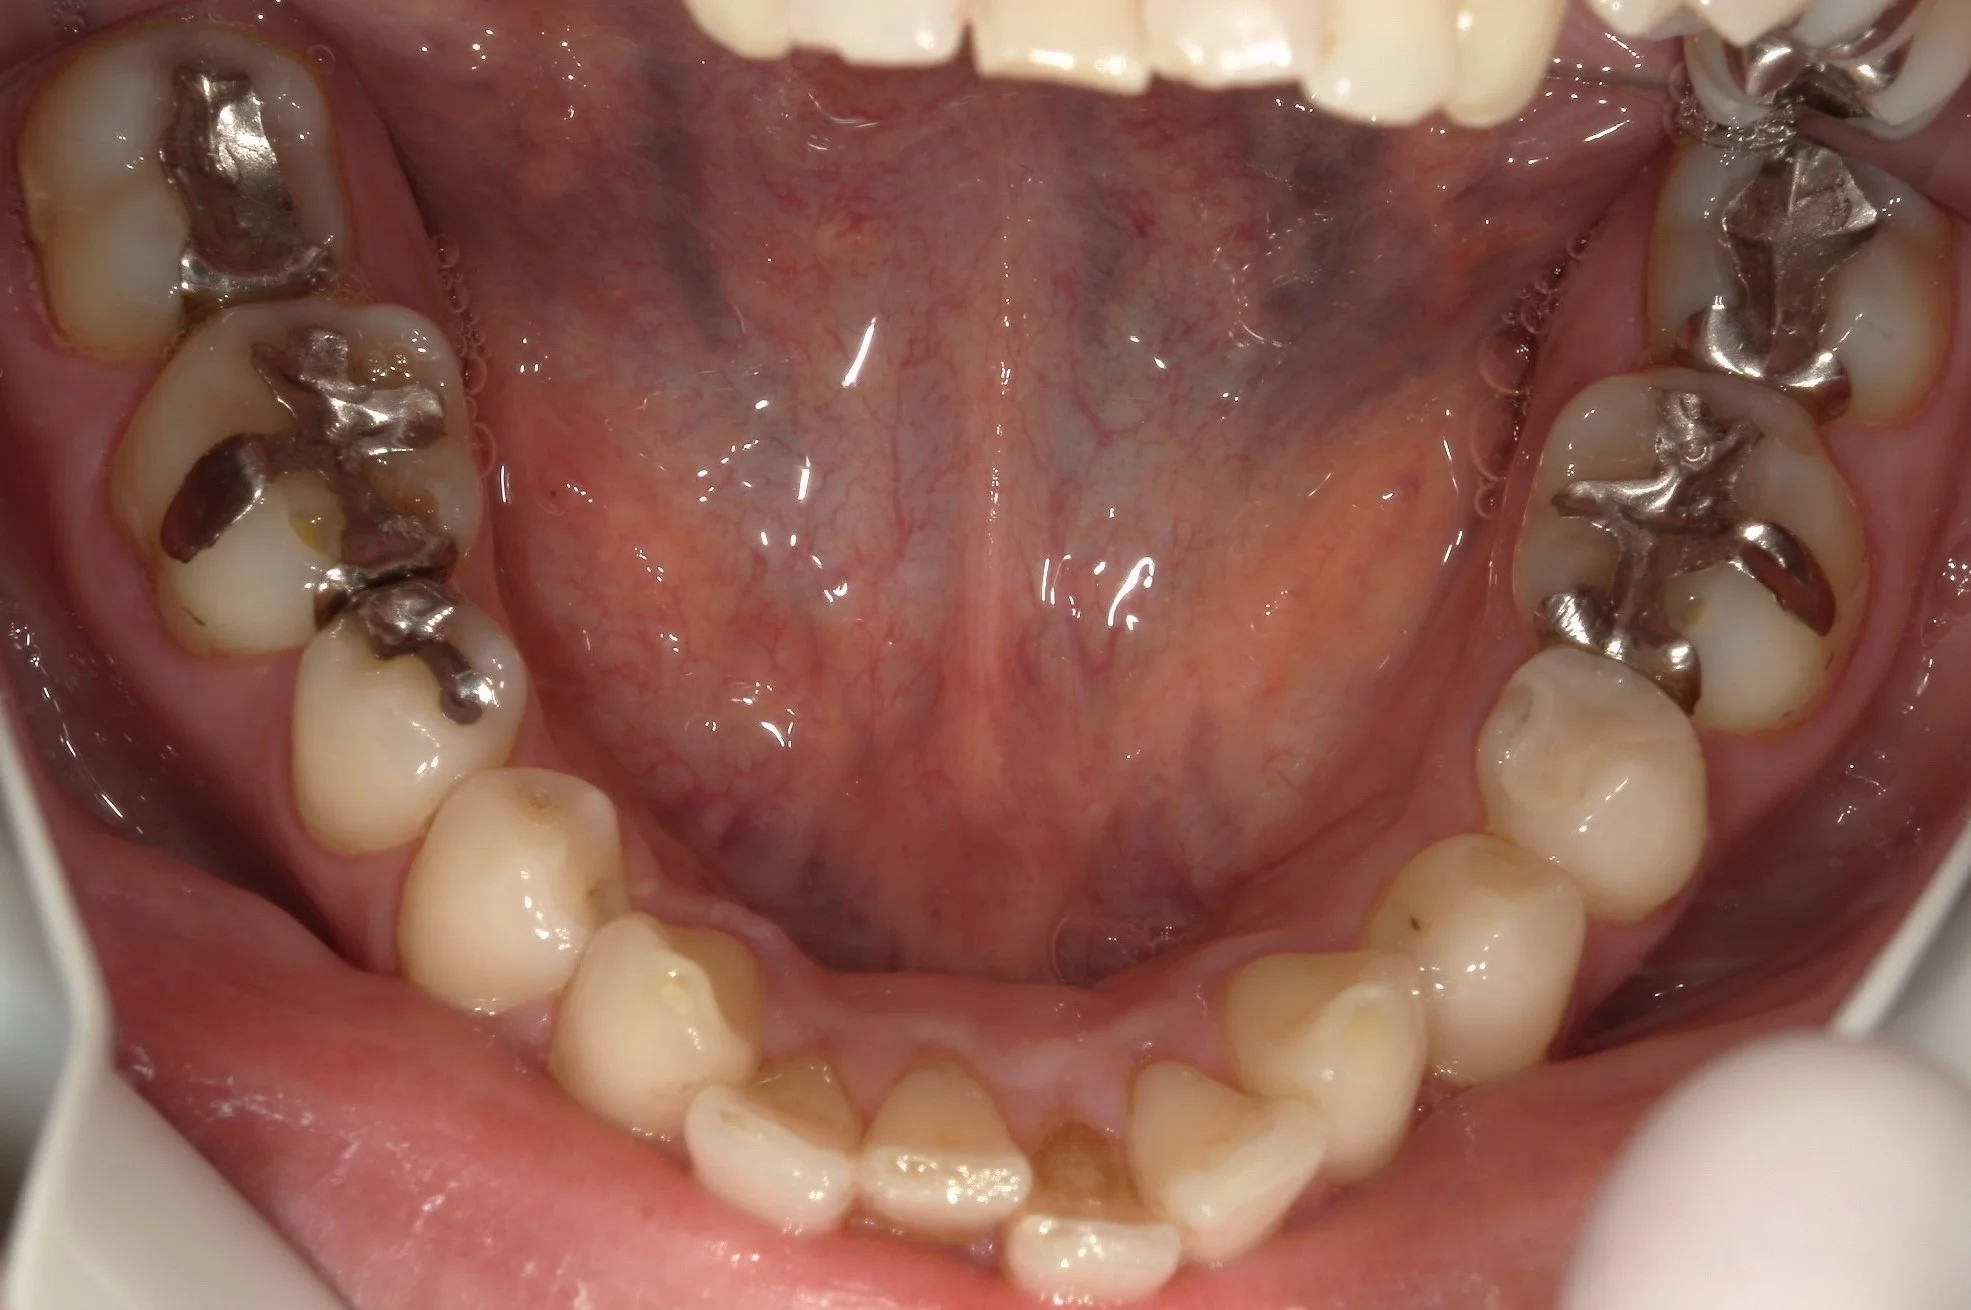

術前の全体の写真がこちらです。

で、術後がこちら。

下の歯は2回に分けて治療しました。

2回で全ての金属が無くなったので、患者さんは非常に喜んでくれましたヽ(゚∀゚)ノ パッ☆